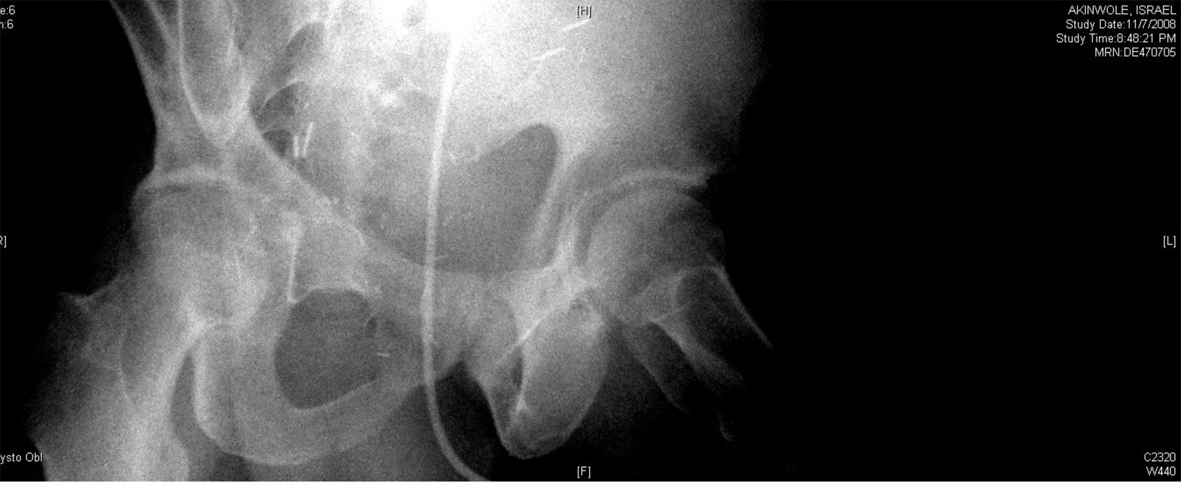

A 54-year-old African American male, presented to our facility with a prostate specific antigen (PSA) of 5.8 ng/mL. Prostate biopsy revealed three cores of Gleason 6 adenocarcinoma. On digital rectal examination he was found to have an approximately 60 g prostate, which was firm and smooth. He underwent an open retropubic radical prostatectomy (RRP). The pathologic specimen showed Gleason 7 adenocarcinoma occupying 20% of the specimen. The stage was T1cN0M0. On the fourth post-operative day, the patient presented to the Emergency Department in another facility complaining of chest pain and shortness of breath. A clinical diagnosis of pulmonary embolism (PE) was made and he was treated with a full dose of IV heparin. He subsequently developed hematuria and complained of lower abdominal pain. On physical exam, he was found to be pale, with diffuse abdominal tenderness, guarding and tachycardia. The patient was then transferred to the Surgical Intensive Care Unit (SICU) at our facility. He received two units of packed red cells. A cystogram showed complete disruption of the UVA with displacement of the bladder neck in the left upper quadrant of the abdomen producing a “pie in the sky” appearance. However, there was no evidence of urinary extravasation indicating an intact bladder neck (Fig. 1, 2). A CT scan revealed a very large pelvic hematoma displacing the bladder neck towards the left upper quadrant (Fig. 3). An IVC filter was inserted to prevent migration of thrombi so that he could discontinue the use of anticoagulants. Patient was managed conservatively for 6 - 8 weeks with gentle traction, and this helped maintaining the bladder neck within the pelvis. A cystogram showed no extravasation of urine. The Foley catheter was removed. The patient voided well initially; however, he developed bladder neck contracture (BNC) after 2 weeks. He was managed with dilation of the bladder neck, but the bladder neck did not return to the pelvis. It was found to be 2 cm away from the urethra, and a “pseudo-tunnel” made of scar tissue was seen between the true bladder neck and the membranous urethra. A surgical approach was used to explore the patient and the “pseudo-tunnel” was resected. Re-anastomosis of the bladder neck with the urethra was performed. The patient has remained continent since then and voids with minimal post void residual urine. There has been no recurrence of BNC (Fig. 4, 5). He needs intra-cavernous injections to help with erections. His post-operative PSA has remained undetectable.

![]() Click for large image | Figure 1. Showing “pie in the sky” appearance of the bladder base with intact bladder neck and no urinary extravasation. |